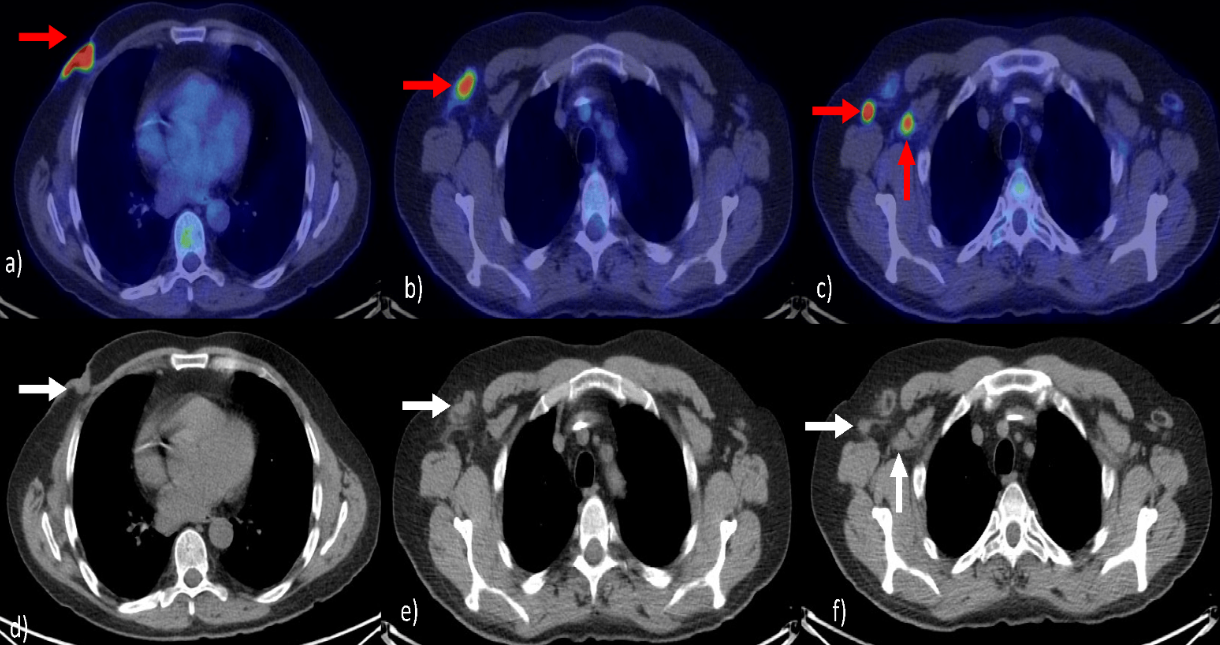

This paper was presented at the 2023 American Society of Clinical Oncology (ASCO) held in Chicago Illinois by Drs Catherine Handy Marshall, Benjamin A. Teply,